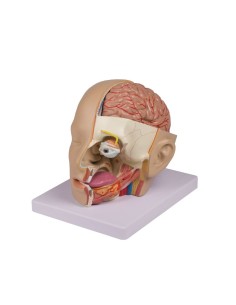

Dal cranio in 22 parti con incastri magnetici ai modelli di colonna vertebrale, da quelli di articolazioni a quelli di cuore, ogni pezzo della nostra collezione è progettato per un’immersione totale nello studio dell’anatomia umana. I nostri modelli, realizzati tramite scansioni di ossa vere, garantiscono un’esperienza tattile autentica e una fedeltà di peso quasi identica agli originali.